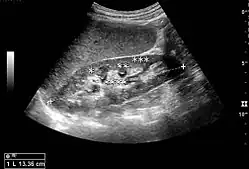

Cortical thickness should be estimated from the base of the pyramid and is generally 7–10 mm. If the pyramids are difficult to differentiate, the parenchymal thickness can be measured instead and should be 15–20 mm (Figure 3). The echogenicity of the cortex decreases with age and is less echogenic than or equal to the liver and spleen at the same depth in individuals older than six months. In neonates and children up to six months of age, the cortex is more echogenic than the liver and spleen when compared at the same depth.[1]

The hydronephrosis is typically graded visually and can be divided into five categories going from a slight expansion of the renal pelvis to end-stage hydronephrosis with cortical thinning (Figure 15). The evaluation of hydronephrosis can also include measures of calyces at the level of the neck in the longitudinal scan plane, of the dilated renal pelvis in the transverse scan plane and the cortical thickness, as explained previously (Figure 16 and Figure 17).[1]